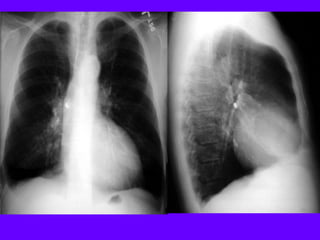

A: Xray shows bilateral bulla.

B: CT shows bilateral bulla.

C: CT after bullectomy.